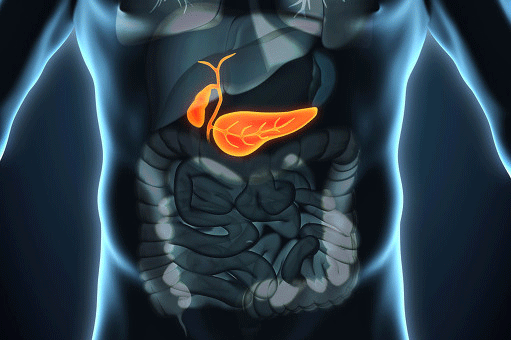

Jun 04, 21 · · 胆囊炎与胆结石的关系 1、关系密不可分,很少单独存在 胆结结石可引起胆囊炎(胆囊结石长期存在或胆囊结石嵌顿于胆囊颈部,引发继发性病变,如:胆囊炎);胆囊炎也可引起胆结石(发生胆囊炎后能促进胆囊结石的形成和增多)。胆囊炎是胆囊的炎症,通常是由结石阻塞胆囊管引起的。 典型的症状表现为腹痛、发热和恶心。 腹部超声检查可以观察到胆囊炎症。 通常可使用腹腔镜切除胆囊。 胆囊是一个体积较小的、梨形的囊性器官,它位于肝的下方。 它贮存胆汁,胆汁是由肝脏产生的可帮助消化的一种液体。 当需要胆汁时,通常是当人们进食时,胆囊收缩挤压胆汁使其经胆管流入小肠胆囊炎的症状一般会比较严重,那么为什么会得胆囊炎呢? 1、肥胖 经过研究发现,肥胖的人患上胆囊炎的几率会比正常人高,所以肥胖也是导致形成胆囊炎的重要危险因素。 2、饮食习惯 生活中过度使用胆固醇食物的人群患上胆囊炎的几率也会比较高,很

膽囊炎 是 細菌性感染 或 化學 性刺激 (膽汁 成分改變)引起的膽囊炎性病變,為 膽囊 的 常見病 。 在 腹部外科 中其 發病率 僅次於 闌尾炎 ,本病多見於35~55歲的中年人,女性發病較男性為多,尤多見於 肥胖 且多次 妊娠 的婦女。Jun 16, 21 · 胆囊炎的症状 1、如果上腹有剧烈的疼痛,很有可能是患胆囊炎的前期症状,所以当你发现自己有腹胀,剧烈疼痛的现象,一定要及时到医院检查 2、如果经常出现恶心,甚至会伴有呕吐,都是有可能进一步确认为胆囊炎的,所以有了此症状一定要及时就医 3、发热,身上冷膽囊炎 (Cholecystitis)是指發生於 膽囊 的 炎症 ,症狀包括右上 腹部疼痛 、噁心、嘔吐、偶有發燒 。 多半在急性膽囊炎之前會有 膽絞痛 的症狀 。